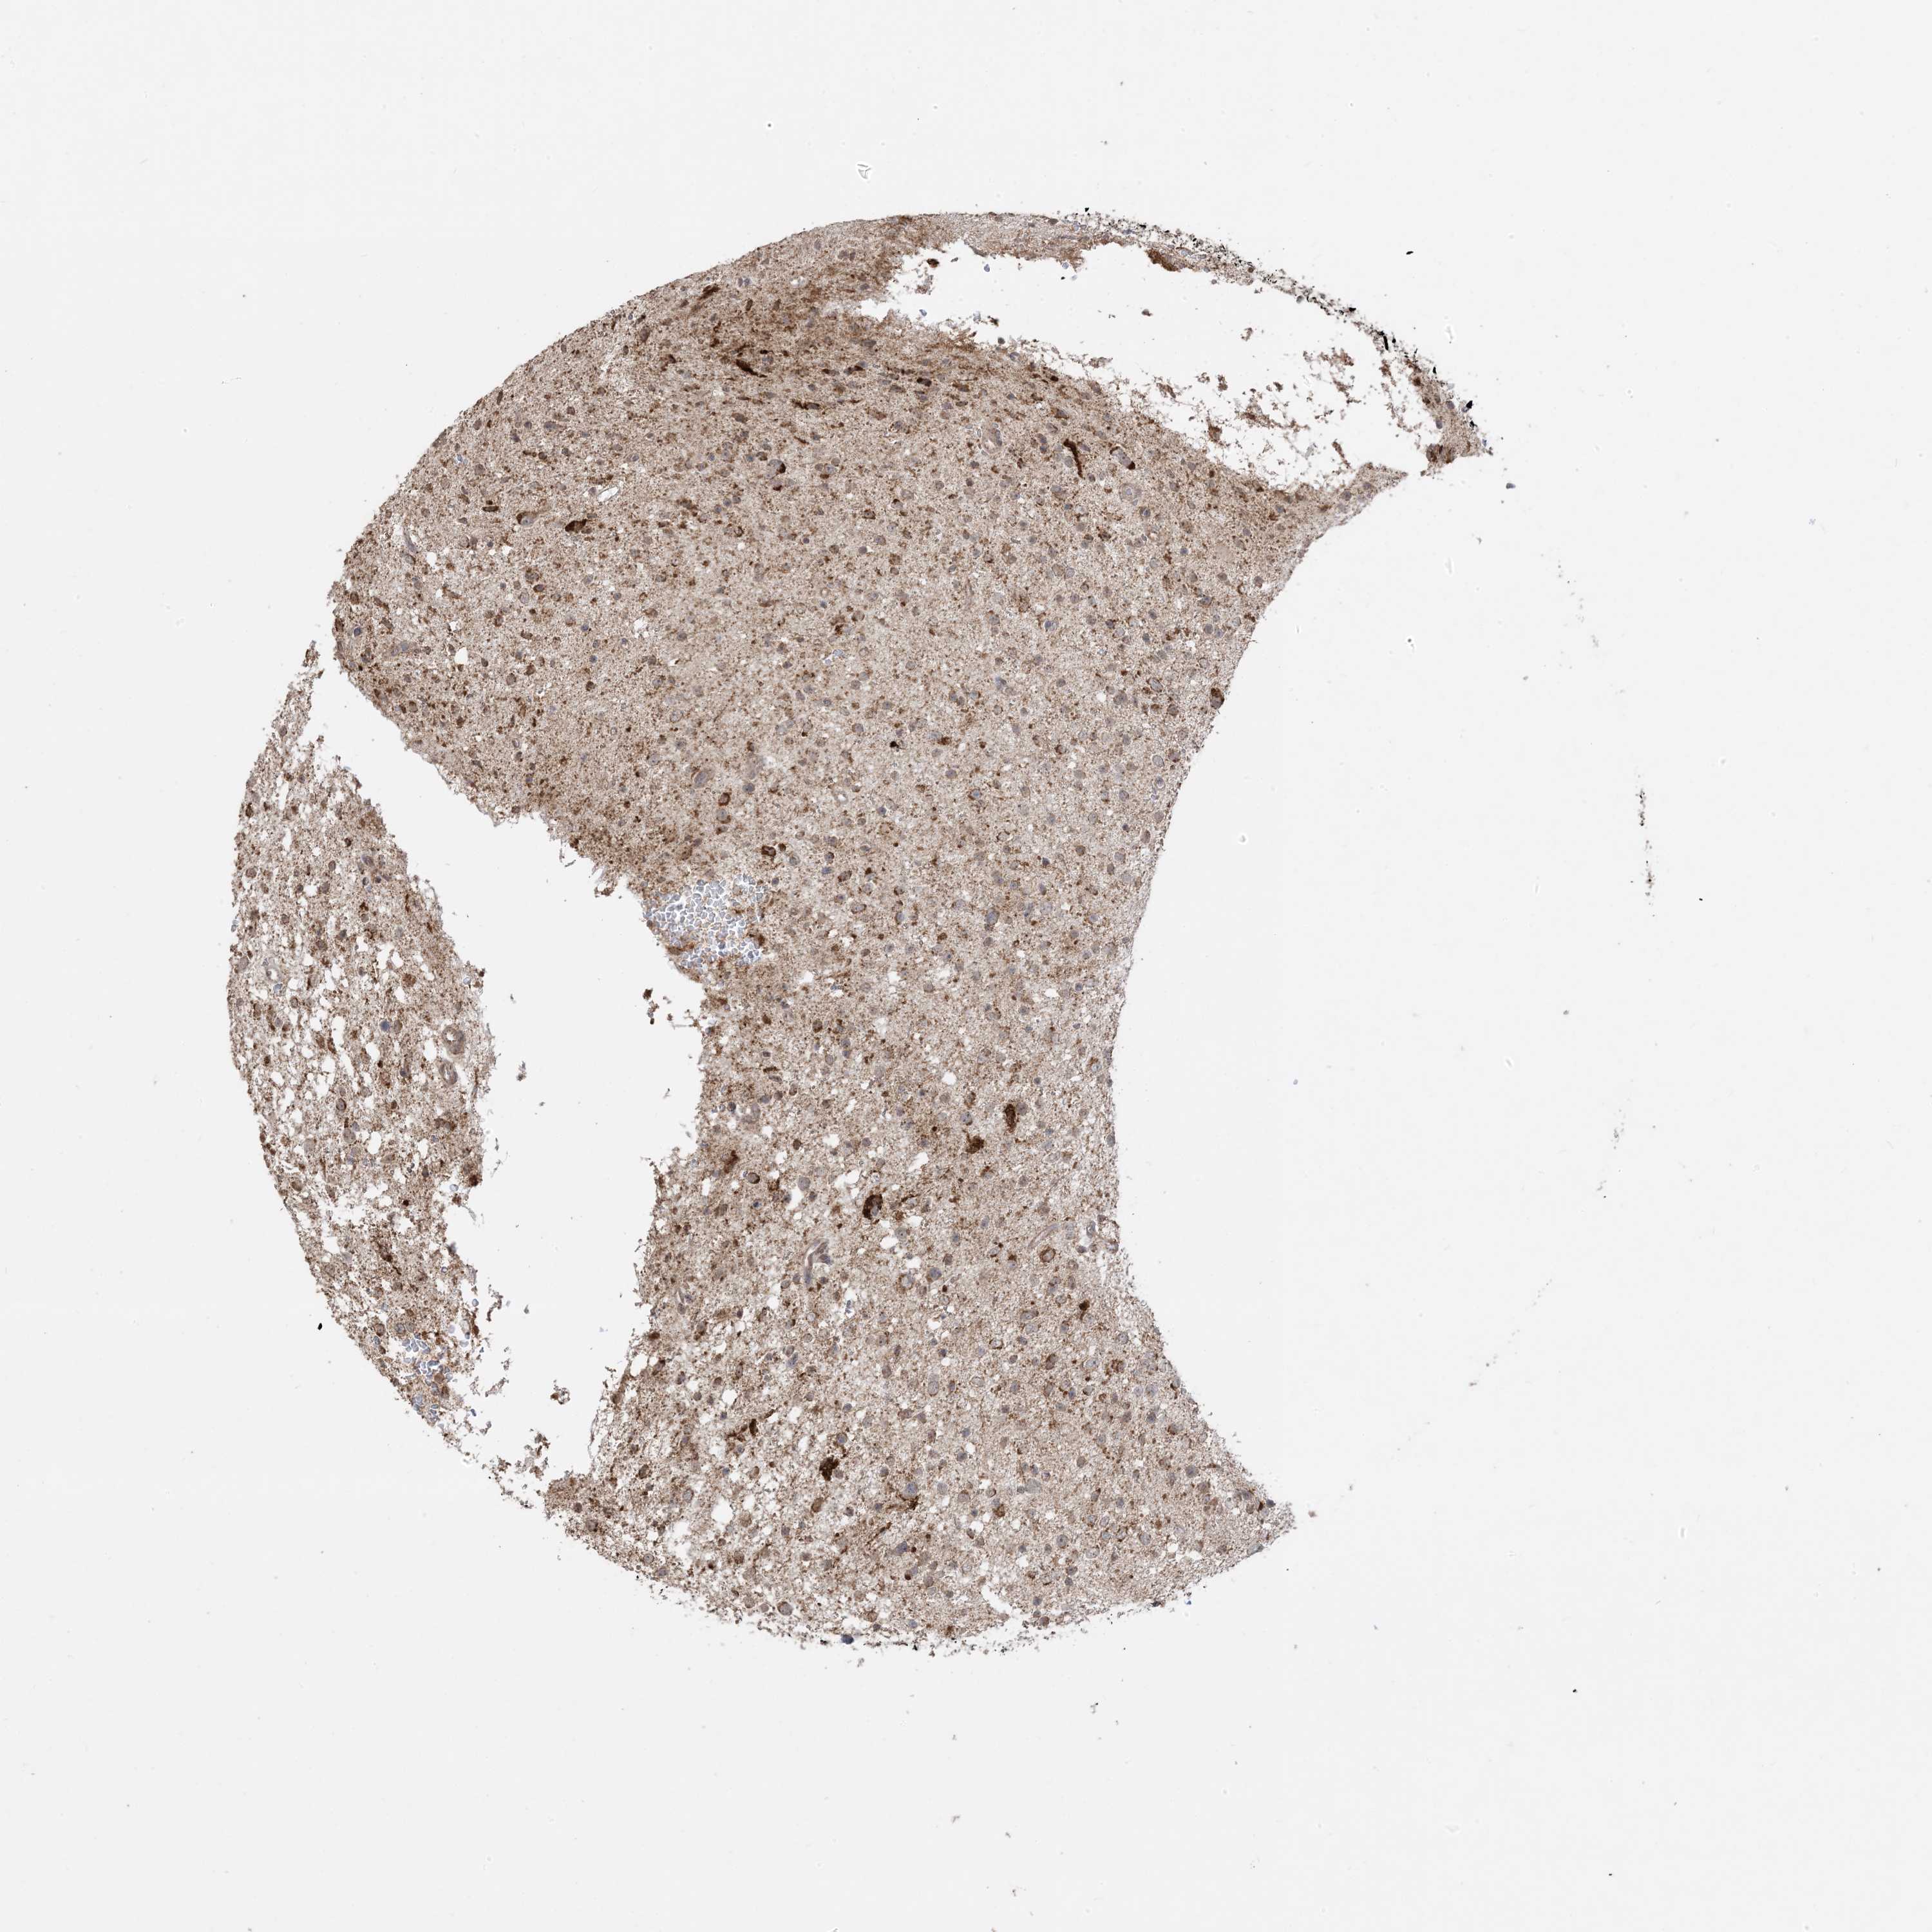

GLIOMA - Protein expressioni

A mouse-over function shows sample information and annotation data. Click on an image to view it in a full screen mode. Samples can be filtered based on level of antibody staining by selecting one or several of the following categories: high, medium, low and not detected. The assay and annotation is described here.

Note that samples used for immunohistochemistry by the Human Protein Atlas do not correspond to samples in the TCGA dataset.

Antibody stainingi

Antibody staining in the annotated cell types in the current human tissue is reported as not detected, low, medium, or high, based on conventional immunohistochemistry profiling in selected tissues. This score is based on the combination of the staining intensity and fraction of stained cells.

Each image is clickable and will lead to virtual microscopy that enables deeper exploration of all samples and also displays staining intensity scores, fraction scores and subcellular localization as well as patient and tissue information for each sample.

Antibody CAB037142

Staining

High

Medium

Low

Not detected

Intensity

Strong

Moderate

Weak

Negative

Quantity

>75%

75%-25%

<25%

None

Location

Nuclear

Cytoplasmic/membranous

Cytoplasmic/membranous,nuclear

Glioma, malignant, High grade

Glioma, malignant, Low grade